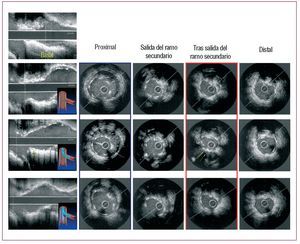

En todos los pacientes se consiguió el éxito inicial del procedimiento. En 1 (4%) caso hubo que implantar un segundo stent en el RS por obtener un resultado subóptimo tras la dilatación. En las tablas 3 y 4 se resumen los hallazgos ultrasónicos en cada estado de los distintos segmentos analizados. En el segmento proximal del stent y a nivel de la salida del RS se produce un incremento significativo del área y una pérdida de la geometría del stent tras el KB (figs. 2 y 3). En el segmento inmediato a la salida del RS se produce cierto grado de deformidad y pérdida de área tras dilatar el RS. Tras el KB se produce un leve incremento del área, aunque no llegaba a recuperarse hasta los valores basales a pesar de que el balón del stent era de mayor diámetro que el del RS y que el inflado se hacía a más atmósferas (12-14 AT en el VP, 6-8 AT en el RS). La figura 4 ilustra los cambios individuales en el área del stent tras cada estado en este segmento. En nuestro estudio no se encontró correlación alguna entre la angulación del RS y el grado de deformidad producido en el bajo rombo tras dilatar aisladamente el RS. En el stent distal, no se objetivaron diferencias significativas en ninguno de los estados.

Fig. 3. Estudio ultrasónico del vaso principal tras implantar el stent, tras dilatar el ramo secundario y tras el kissing. En azul queda encuadrado el segmento proximal del stent, que muestra su falta de aposición (flechas blancas), que queda corregida tras el kissing. En rojo queda encuadrado el segmento distal a la salida del ramo secundario, que se deforma tras dilatar el ramo secundario (nótese en el eje largo la deformación señalada con flechas amarillas), y tras el kissing mejora, aunque no consigue llegar al estado basal.

En 1 (4%) se objetivó falta de aposición del stent en el segmento proximal tras implantar el stent y tras dilatar el ramo secundario, pero se consiguió una correcta aposición tras el KB (fig. 3). Por lo tanto, el KB disminuye las posibilidades de mala aposición proximal del stent, aunque este defecto fue infrecuente en nuestra serie. Por otro lado, se debería tener en cuenta el incremento de área y la deformación producida por el KB en la era de los stents farmacoactivos, ya que podrían afectar a la estructura del polímero, con la consecuente pérdida de beneficios de este tipo de stent.

Si analizamos el segmento inmediato a la salida del RS, observamos que se produce una deformación en la geometría del stent (el IS pasa de 0,82 a 0,74; p < 0,01) y una discreta pérdida del área a dicho nivel, pasando de 5,9 ± 1,2 a 5,23 ± 1,1 mm2 (p < 0,05), lo que supone una pérdida del 12% del área del stent. Sin embargo, el espectro de deformación del stent en el bajo rombo es amplio, y varía desde casos en los que no se produce modificación alguna (fig. 2) a otros en que la deformación es más marcada (fig. 3). Quizá el diámetro del balón utilizado para dilatar el RS, el grado de angulación o la pata metálica por la que pasan la guía y el balón podrían modificar el grado de deformación del bajo rombo, y sería interesante determinar los posibles factores que influyen en dicha deformación en estudios ulteriores. En nuestro estudio no se encontró correlación alguna entre la angulación del RS y el grado de deformación en el bajo rombo (r = 0,32; p = 0,1). Además se dividieron los casos en ángulos > 60° y < 60°, y analizamos la pérdida de área del stent tras dilatar el RS y el grado de recuperación tras el KB; no se encontraron diferencias entre los dos grupos. En 6 (26%) casos, el área del stent osciló entre 4 y 5 mm2 y sólo 3 (14%) quedaron con un área luminal < 4 mm2, cifra por encima de la cual se considera poco probable que se produzcan defectos de perfusión14-18.